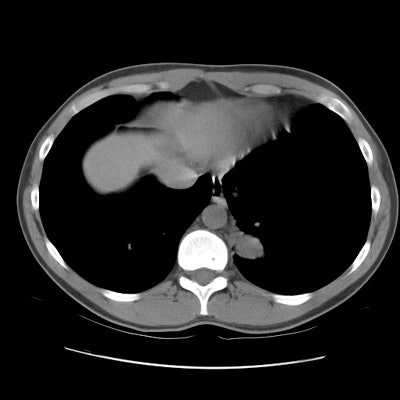

The patient below presented for evaluation of an abnormal CXR which demonstrated a left retrocardiac mass. (Click image to enlarge)

CT scan revealed a soft tissue mass in the left posterior-medial lung which had a branching tubular appearance. Some associated para-emphysematous changes were noted. (Click images to enlarge)